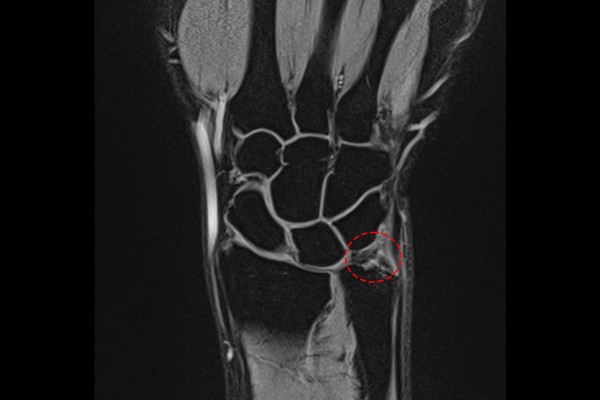

병력청취 후 신체진찰을 위해 새끼손가락측 손목을 눌렀을 때 통증(압통)이 발생하였고, 손목을 가측으로 누르면서 돌렸을 때 역시 통증이 발생한 것을 확인하였습니다. 정확한 상태를 파악하기 위해 환자분께서 지참해오신 MRI 사진을 봤을 때, 삼각섬유연골 복합체(TFCC) 부근에 하얗게 신호변화를 확인하여, 손목 인대파열이 아닌 우측 손목 가측 삼각섬유연골 복합체 손상(TFCC injury wrist Rt.)을 진단하였습니다.